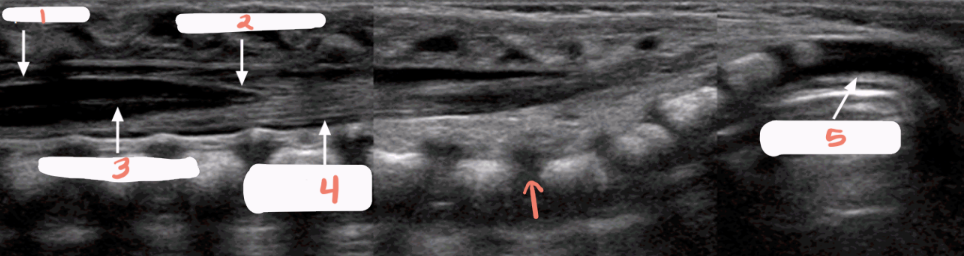

1

spinal cord

2

subarachnoid space

3

arachnoid and dura mater

4

cartilaginous spinous process

5

conus medullaris

6

central echo complex in hypoechoic spinal cord

7

vertebral bodies

8

nerve roots forming the cauda equina